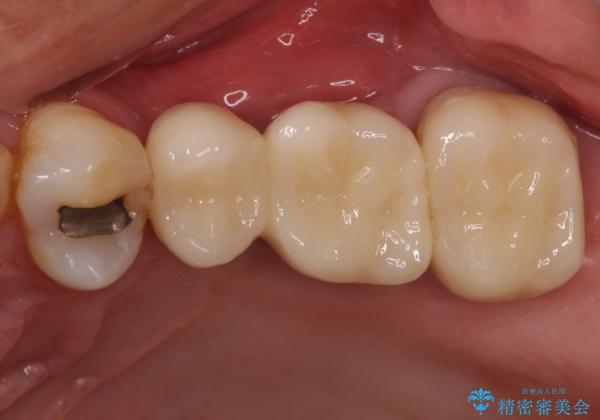

部分矯正を併用した奥歯のインプラント補綴治療

- 奥歯を他院で抜歯した後、インプラント治療を希望とのことで来院された患者様です。

ブリッジの支台を抜歯したことで2本のインプラントが必要であり、その後方はインプラント埋入に必要な骨量が不足していたため、上顎洞粘膜の挙上を行うこととしました。

また、残っている最後方歯は手前に倒れてきていたため、部分矯正により奥に移動させてから、インプラント埋入を行うこととしました。

部分矯正期間中はアンカースクリューやフック、ゴムなどが粘膜にあたり、大変な思いをすることになりましたが、そのおかげでインプラント補綴した歯と最後方歯の位置が非常に良好となり、まるでご自身の歯のように咬むことができるようになりました。